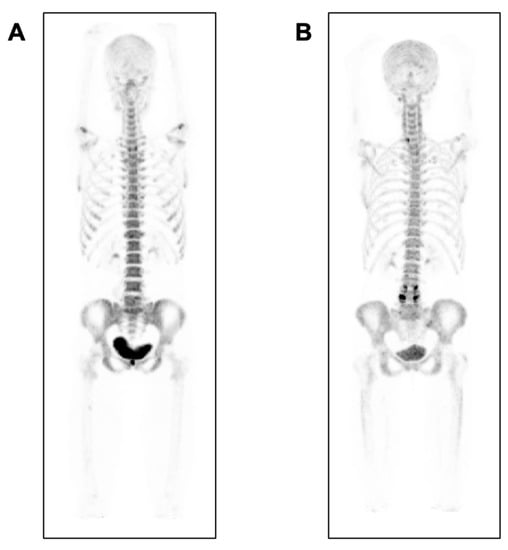

- Eekhoff, E.M.W.; Botman, E.; Coen Netelenbos, J.; De Graaf, P.; Bravenboer, N.; Micha, D.; Pals, G.; De Vries, T.J.; Schoenmaker, T.; Hoebink, M.; et al. [18F]NaF PET/CT scan as an early marker of heterotopic ossification in fibrodysplasia ossificans progressiva. Bone 2018, 109, 143–146. [Google Scholar] [CrossRef]